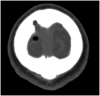

Hyperpneumatization is a rare pathological process where air-filled cavitation form within solid bone architecture occurring at sites where physiological pneumatization is not seen. Extension of this process into the atlanto-occipital region is considered extremely rare and is only quoted several times in the literature. In this case report, we present a 66-year-old man who presented with an 8-month history of a worsening frontal headache and blocked sensation in his left ear. Subsequent CT head evaluation revealed hyperpneumatization affecting C1 vertebra, temporal and occipital bones with extension into the clivus. A rare complication of epidural emphysema was seen. The aetiology of hyperpneumatization is uncertain, although it is thought to be either congenital or acquired. In our case, clinical suggestion of eustachian tube dysfunction and radiological findings of thickened sinus mucosa and a unilateral nasal polyp point to chronic recurrent coryzal illnesses, which may indicate an acquired mechanism. Management is mostly conservative with surgical management reserved for high risk or refractory cases.